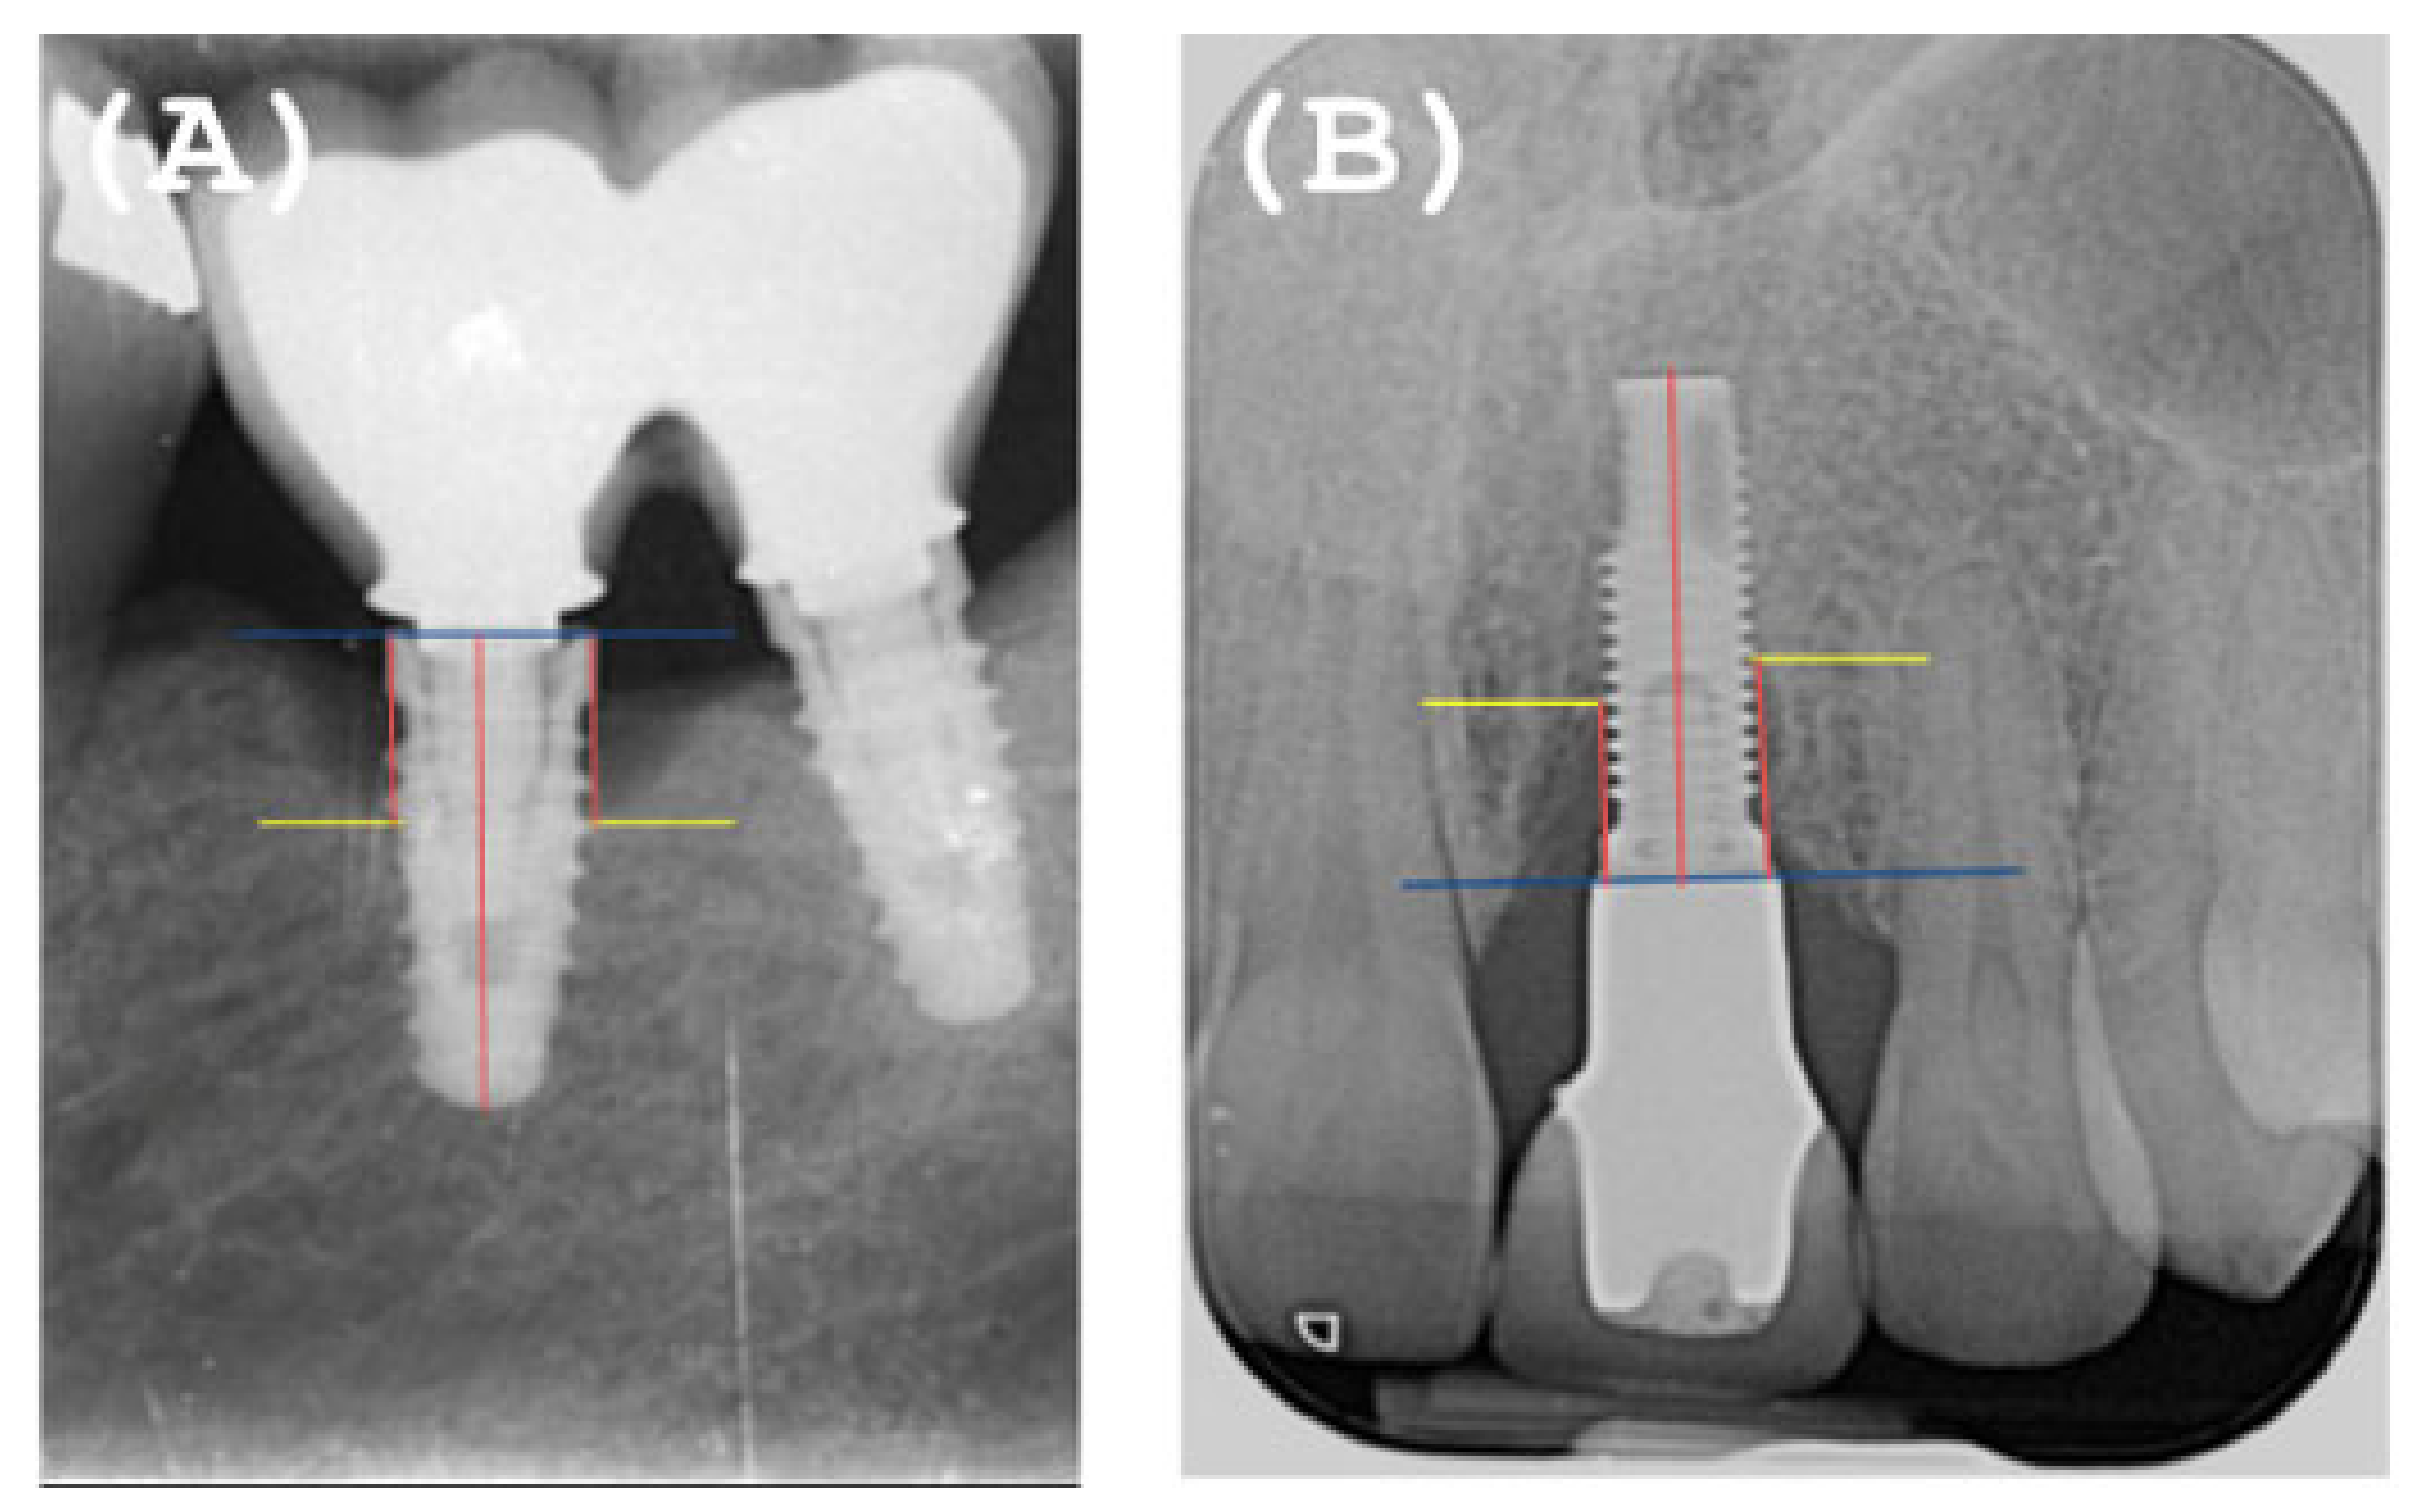

- Overcontoured or non-overcontoured prostheses: assessed by periapical radiographs and clinical evaluation by a calibrated examiner, where an overcontoured prosthesis is more associated with inflammation and the retention of bacterial plaque compared to prostheses with an adequate contour (Figure 1).